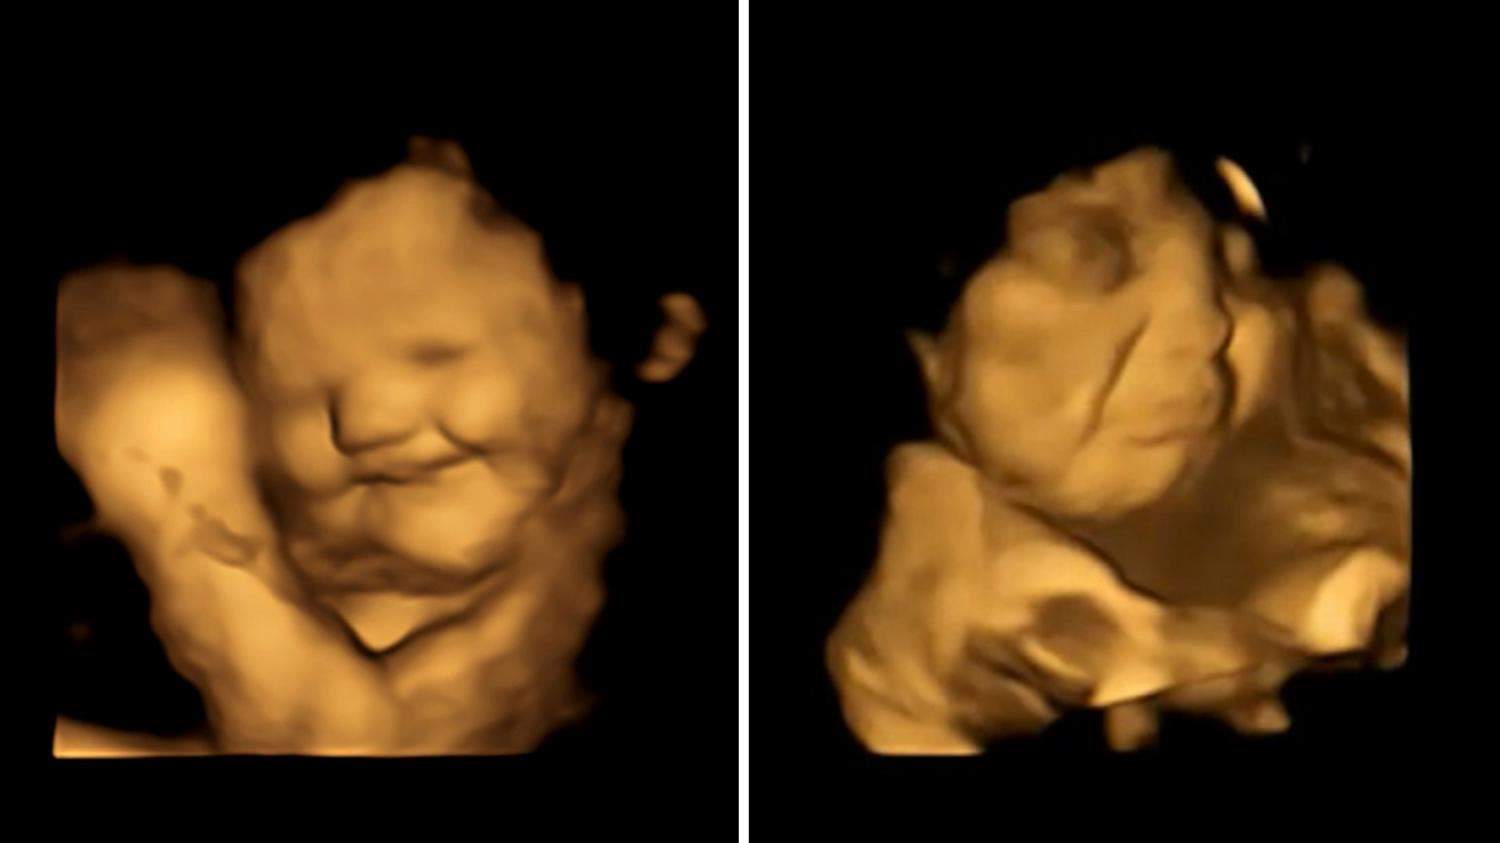

في دراسة مذهلة تمكن علماء من رصد وجوه الأجنة وهم  يتناولون الطعام في بطون أمهاتهم بسبب نوعية الطعام ،فقد لاحظوا أن الجنين يبتسم حين يتذوق الجزر ويعبس عندما يكون اللفت والكرنب أو  هو الطعام،

وكشفت الدراسة أن الأجنة في الرحم يتفاعلون بشكل إيجابي مع أمهاتهم اللواتي يأكلن الجزر، ولكنهم يبكون بعد تناول الأمهات للخضروات الخضراء.

وبحسب شبكة "سكاي نيوز" البريطانية، قام الباحثون في جامعة "دورهام" بأخذ موجات فوق صوتية رباعية الأبعاد لـ100 امرأة حامل، بعد 20 دقيقة من تناول أقراص مليئة إما بمسحوق الجزر وإما بالكرنب.

ووجدوا أن الأجنة التي تناولت أمهاتها أقراص الجزر تبتسم بعد ذلك بوقت قصير، لكن مسح النساء اللواتي تناولن أقراص الكرنب أظهر أن أطفالهن يبكون.